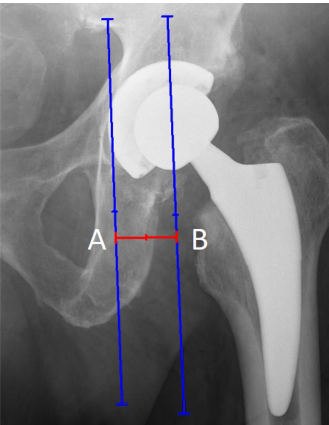

股骨偏心距 (Femoral offset)

股骨偏心距定义为从股骨头旋转中心 (COR) 到平分股骨长轴的直线的距离。恢复的股骨偏心距通过改善髋关节的屈曲和内旋来增强生物力学,例如外展肌力和活动范围 (range of motion, ROM)。

此外,在健侧正常值5 mm范围内恢复股骨偏心距可减少聚乙烯衬垫的线性和容积磨损。未能将偏心距恢复在 < 5 mm 范围内可能导致疼痛加剧和关节恶化。偏心距减小会降低软组织张力,并易导致脱位。根据研究,位置良好的股骨偏心距可能是防止THR术后脱位的关键机械因素。然而,目前仍未确定哪些股骨偏心距值是翻修的指征。

股骨偏心距测量。 A. 穿过COR的线;B. 平分股骨长轴的线